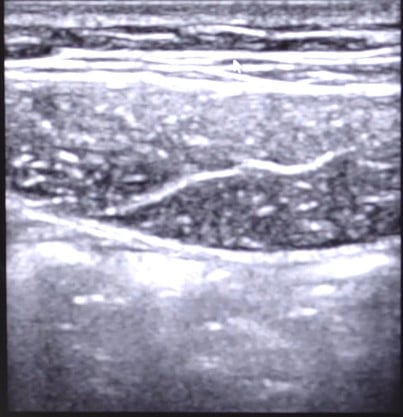

Uso da ultrassonografia no diagnóstico das hérnias inguinais

A ultrassonografia se destaca como método diagnóstico no caso das hérnias inguinais, apresentando uma taxa de 97 a 100% na detecção de presença de hérnias e taxa de 60 a 86% no diagnóstico do seu tipo.

O exame de ultrassonografia para avaliação da região inguinal utiliza um transdutor linear de alta frequência e inicia-se com o paciente em decúbito dorsal, a região inguinal e a força ilíaca direita ou esquerda exposta. Se houver alta suspeita de hérnia inguinal e não houver detecção da patologia com o paciente em decúbito dorsal, faz-se necessário examinar o paciente em pé.

O exame deve começar próximo da região inguinal, com o transtudor colocado na projeção do músculo reto abdominal. Deve-se então identificar os planos parietais e procurar os planos que servem de marco para a realização do exame. Eles estão apresentados na imagem abaixo:

Ainda nessa região, no momento da realização do exame, é importante que o médico conheça e reconheça o ligamento inguinal, que se estende da espinha ilíaca ântero-superior ao púbis. Ele será útil para a diferenciação entre a hérnia fermoral e a hérnia inguinal.